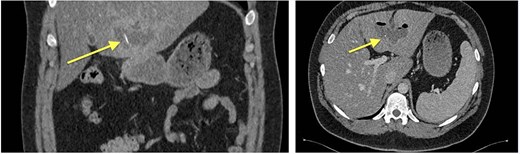

Four months later, a 33-year-old man presented with fever and weakness of unknown origin for 5 days. He was barbecuing a lot in the last weeks, as he was on vacation. Epigastric tenderness was present at admission. Laboratory parameters showed elevated inflammatory markers. CT scan (Fig. 3) showed a liver abscess with a metal foreign body.

Eventually, diagnostic laparoscopy showed a small posterior gastric perforation next to the liver abscess with migration of the metal bristle into the liver, causing the abscess. Consecutively, surgical drainage of liver abscess, recovery of the foreign body, and gastric perforation repair with sutures were performed (Fig. 4). No postoperative complications occurred. The patient received intravenous antibiotic treatment for 10 days, followed by oral antibiotics for another 4 days. Follow-up showed decreasing CRP and WBC and rapid recovery after surgery. On the 4th postoperative day, the patient could be discharged.